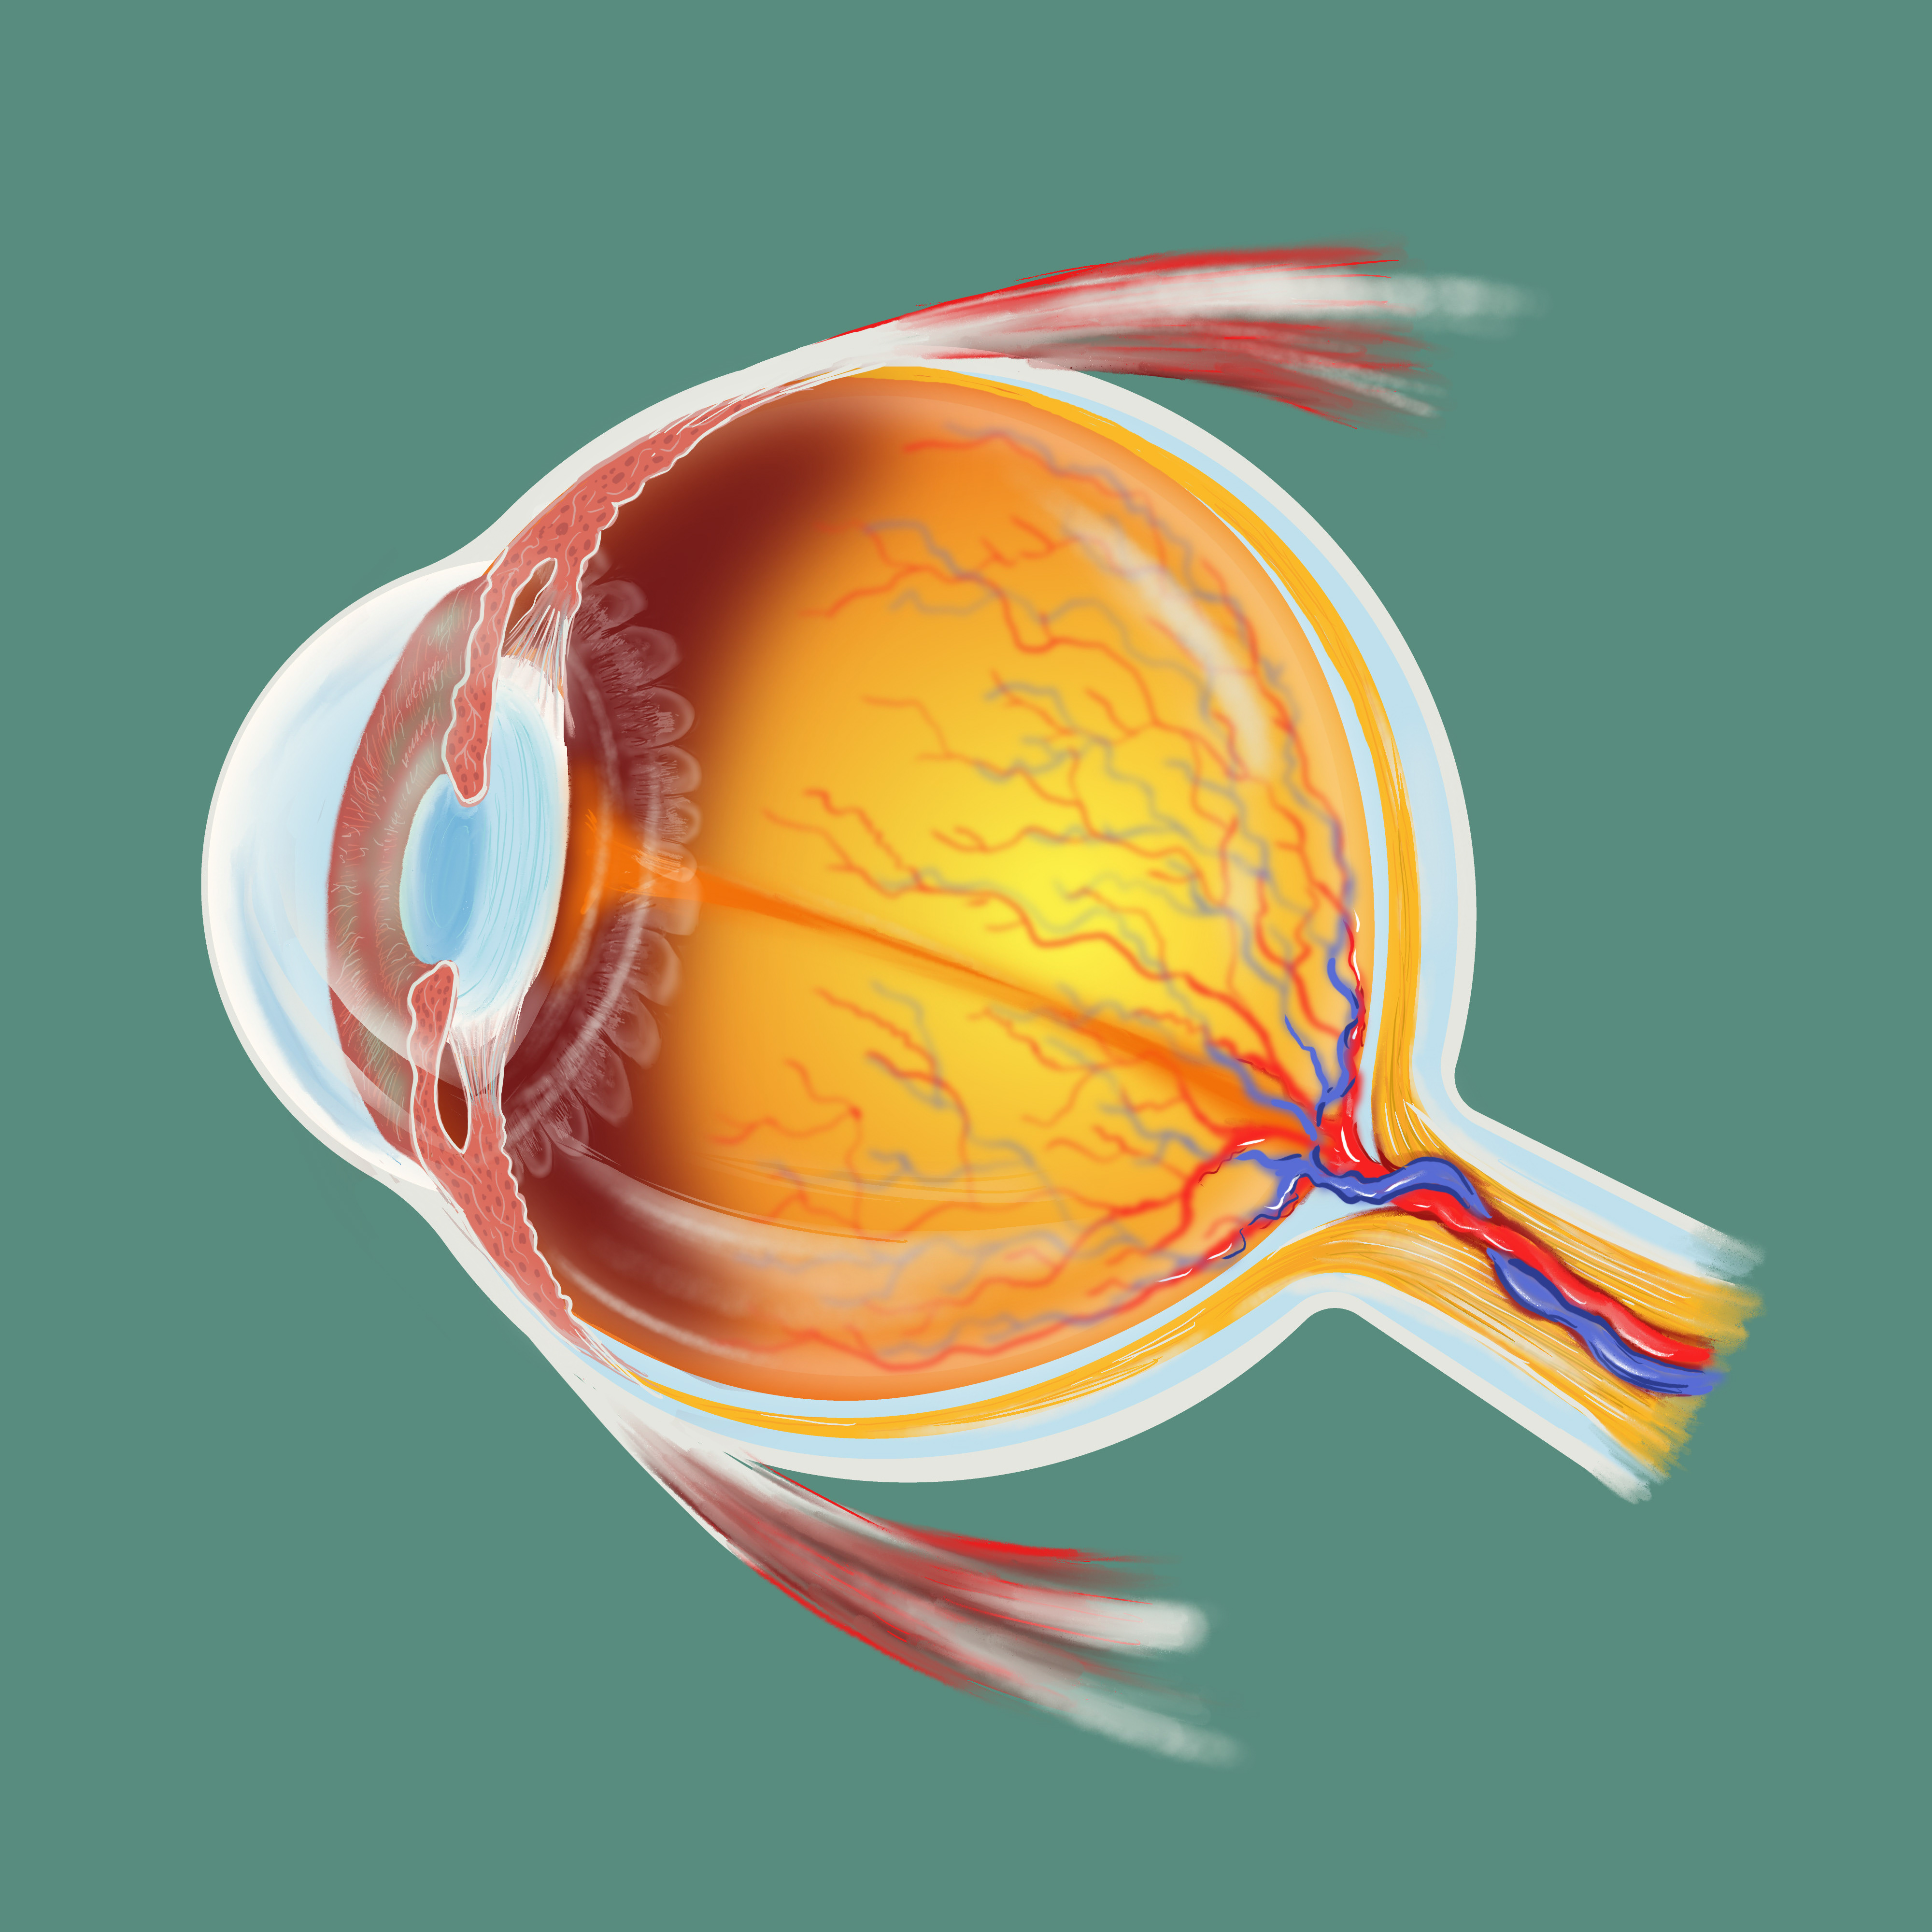

Anatomía ocular

Proceso / Oftalomología